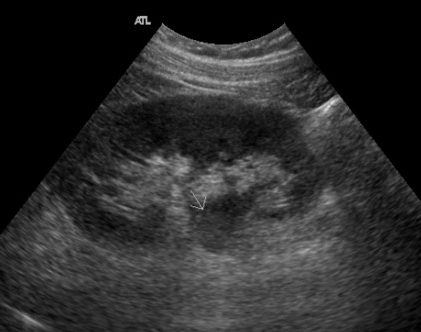

En neonatos, la ADPKD puede mostrar riñones agrandados con múltiples quistes de diferentes tamaños en la corteza y la médula renal. La ecogenicidad cortical puede estar aumentada y la diferenciación corticomedular puede estar disminuida o ausente en casos severos. Aunque la ADPKD es más comúnmente diagnosticada en adultos, puede ser detectada prenatalmente en algunos casos.[1-2]

En la ARPKD, los riñones suelen estar agrandados y presentan una ecogenicidad aumentada con una pobre diferenciación corticomedular. Los quistes son generalmente pequeños y numerosos, distribuidos en la corteza y la médula, lo que puede dar una apariencia de «sal y pimienta» en la ecografía. Esta condición puede estar asociada con oligohidramnios y características de síndrome de Potter debido a la compresión fetal.[4]